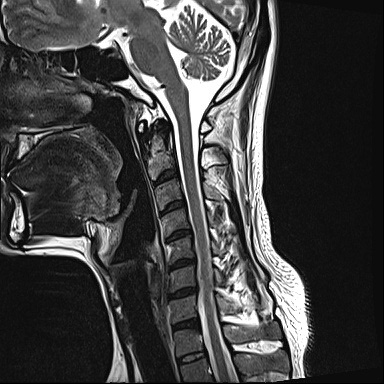

Ű 177 64 40 ()ijħ ڸǥغ ǥغ ϱ ȣϴ 1C.ٸǷ 6C.ڸ 6C.ھ Ḳ 6C.ڻ ()ũ( ߰Ż) ڸ(߹) ĿCڸ(ĸ) Ը ũ(߰Ż)ġ, , Ḳ ġ Ǵ ġ ()ijħ ڸǥغ ǥغ ϰ ߴ ġ 2008~2011 ð ɾƼ ǻ ۾ Ҷ, Ʈ , ȸ ϰ, . 2011 4 : 6,7 ߰Ż , ڸ ó ļ ַ ġ . ü, ߳, ѹ, ũ, ֻġ ġ غ ȿ ġ ġᰡ Ұ Ǵϰ ֿ 3ȸ ƮĪ ణ ȣ. 2014 5 20 濡 ħ ڱ ϰ · ư. (ֱ ϰ, Ʈ ϰ ) а ũ ִ ֺ, Ʒ κп δֻ 1ȸ ̰, ణ . ûϸ鼭 ȸԲ ϴ ûϰ ߽ϴ. Ϻϰ ȸ ּ. mriԴϴ. |